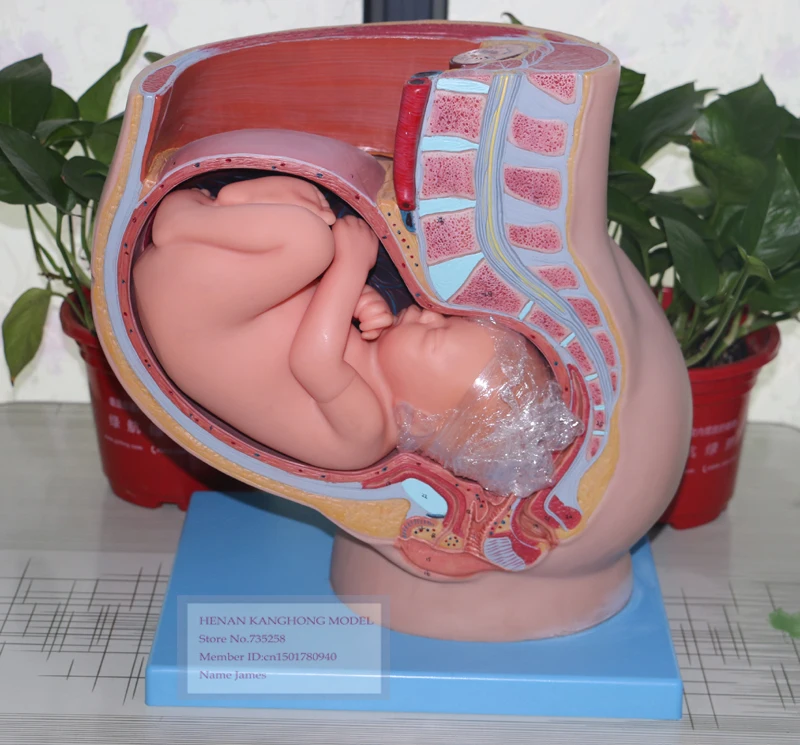

Физиология беременности: строение органов

Раздел: Моменты озарения